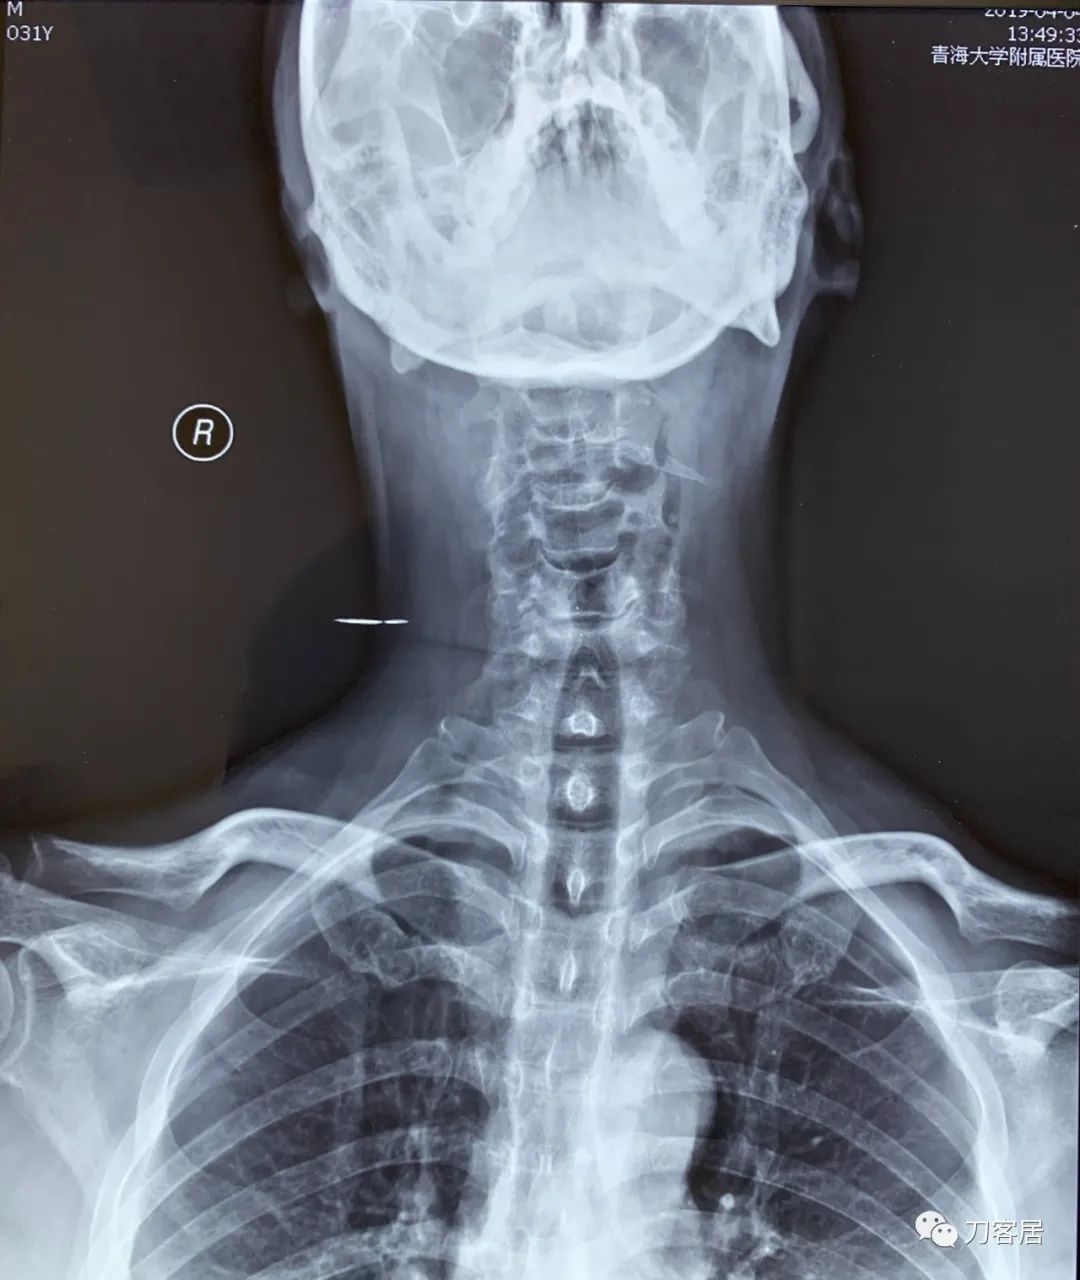

图5. 20160328西宁骨伤烧伤专科医院颈椎6位X线片

图8. 20190404青海大学附属医院颈椎正位X线片

图9. 20190404青海大学附属医院颈椎侧位X线片

图10. 20190404青海大学附属医院颈椎过屈位X线片

图11. 20190404青海大学附属医院颈椎过伸位X线片